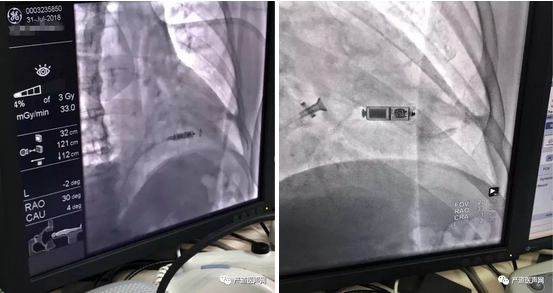

术后查看造影

植入术后X线留影